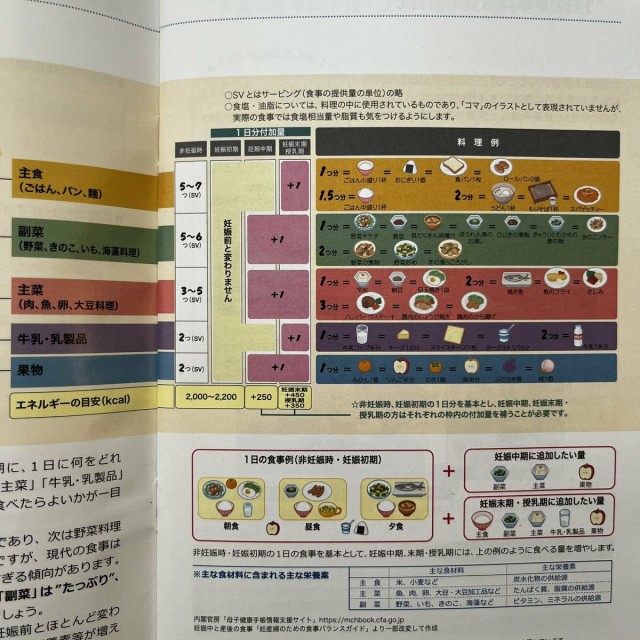

妊娠中の食事 妊娠後期+産後の食事量 一回の食事でお米なら200gっていわれたけど市販のパックご飯でも150gが普通で大盛りだと180gなのに鬼畜すぎない? プラス副菜と主菜……. 毎食パスタにしても足りない量www 分けて食べましょうって言われたけどおにぎりにしたら7個くらいになるよ?